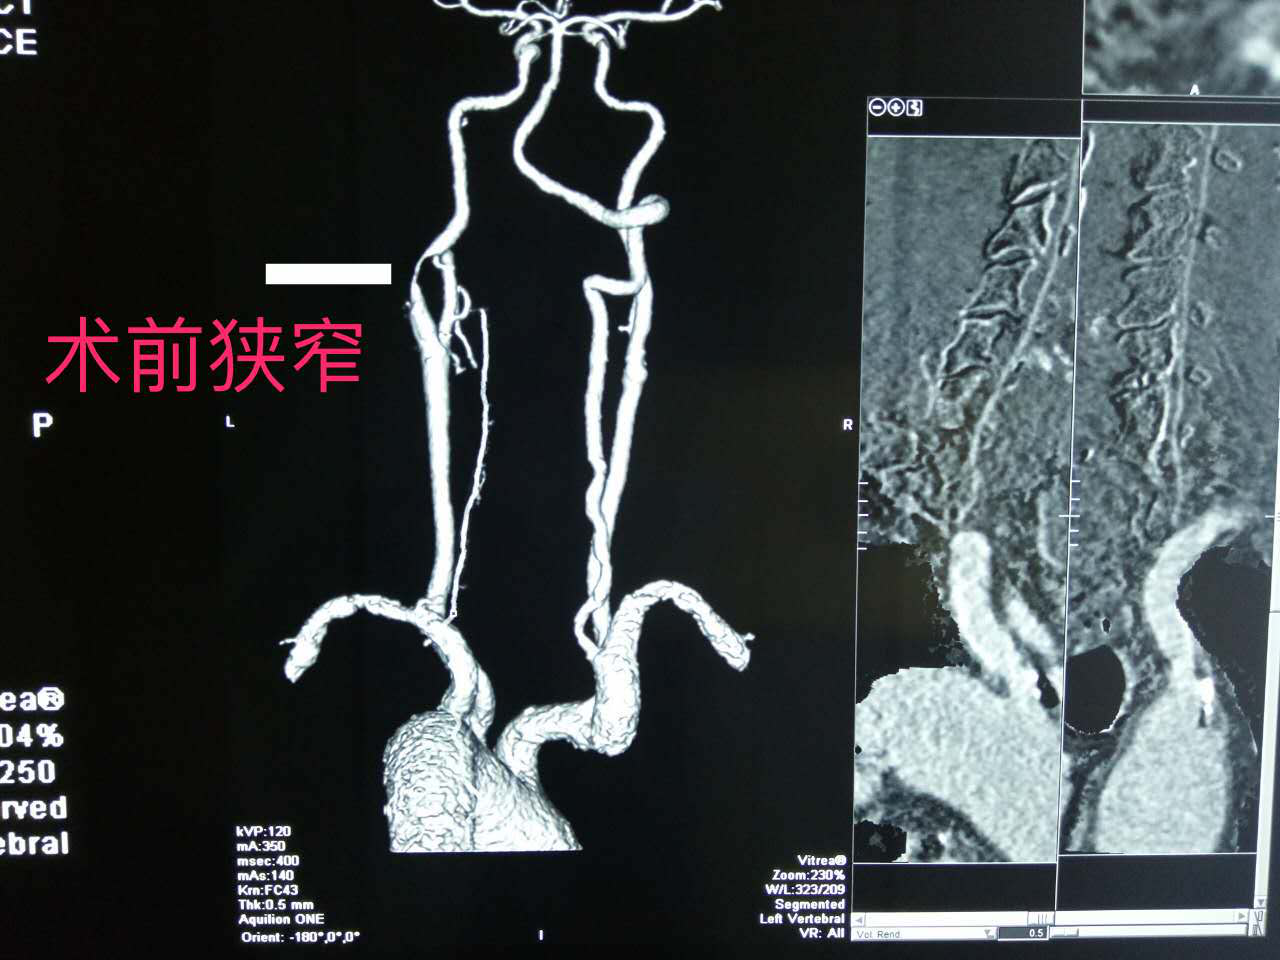

无症状颈动脉狭窄需要治疗吗

1280x960 - 761KB - PNG